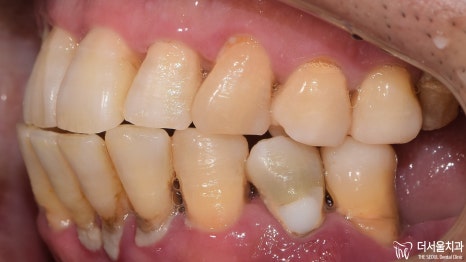

2) 측면

이쪽도 정면과 마찬가지였습니다.

구강 내에 전체적으로 번진 치주 질환 때문에

잇몸 및 치아의 상태가 좋지 않습니다.

3) 교합면

발치를 하셨기 때문에 텅 비어 있는 곳이 많았습니다.

하악 전치부 쪽이 심각한 것으로 판단이 되네요.

처음 검진을 했을 때 보다

더 심각한 구강상태를 갖고 있었습니다.